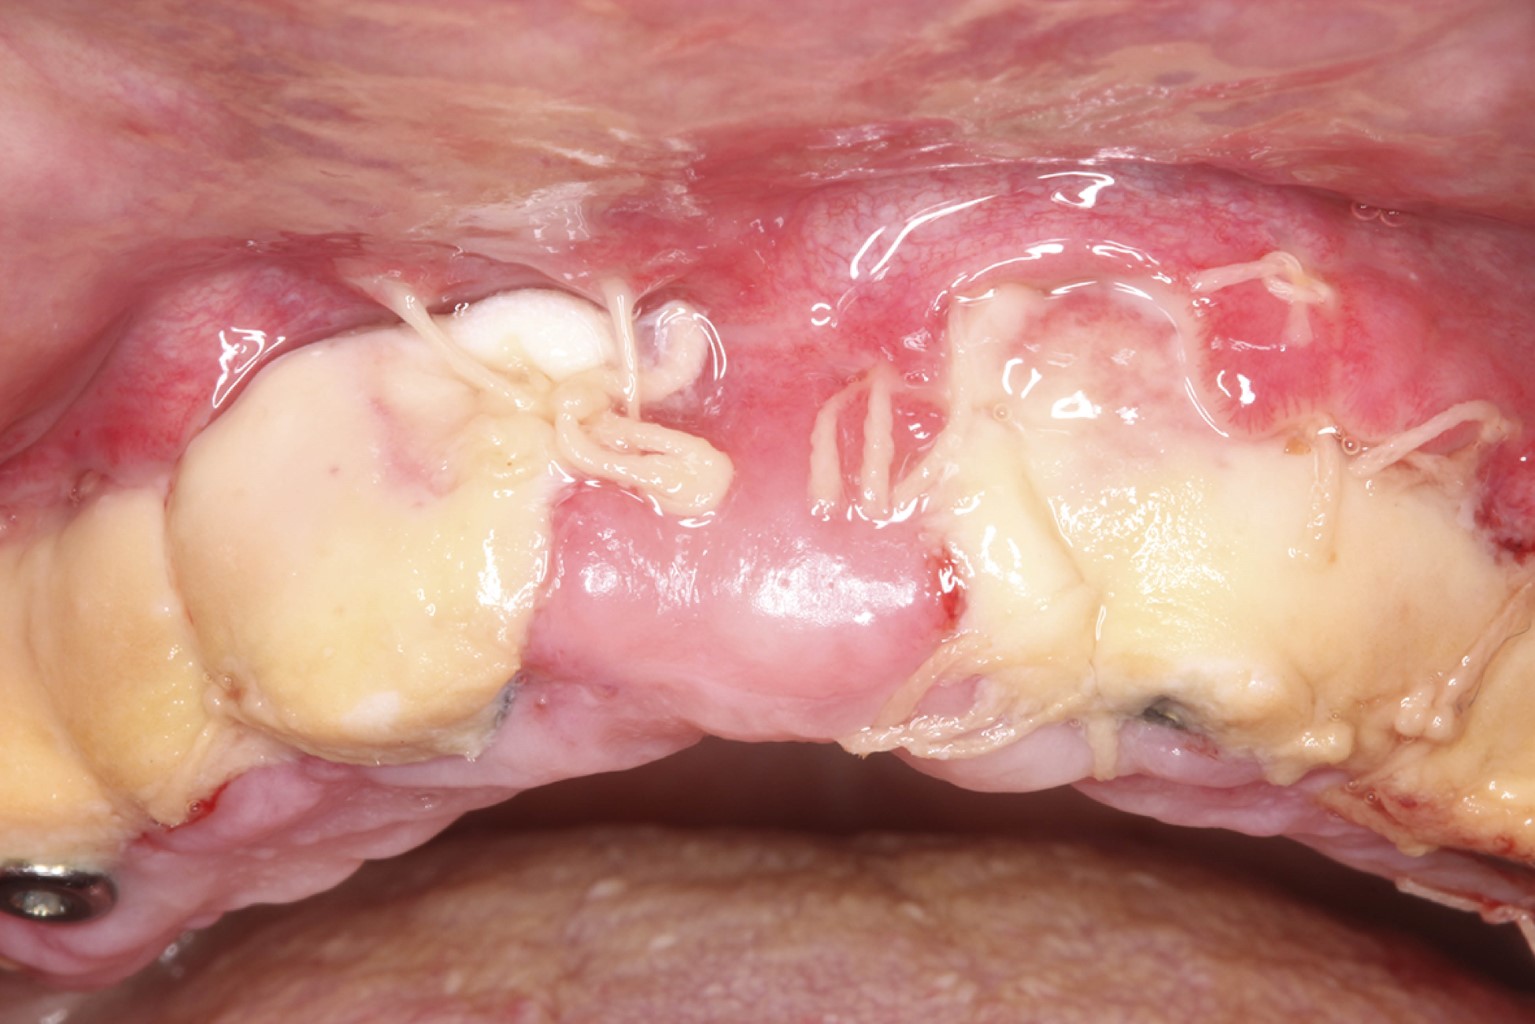

Se estabilizó el injerto fijando primero los extremos distales con puntos simples y posteriormente se estabilizó en apical suturando al periostio con Vicryl 4-0, se colocaron puntos suspensorios en la porción coronal, suficientes para asegurar la inmovilidad del injerto (Figura 3).

Figura 3